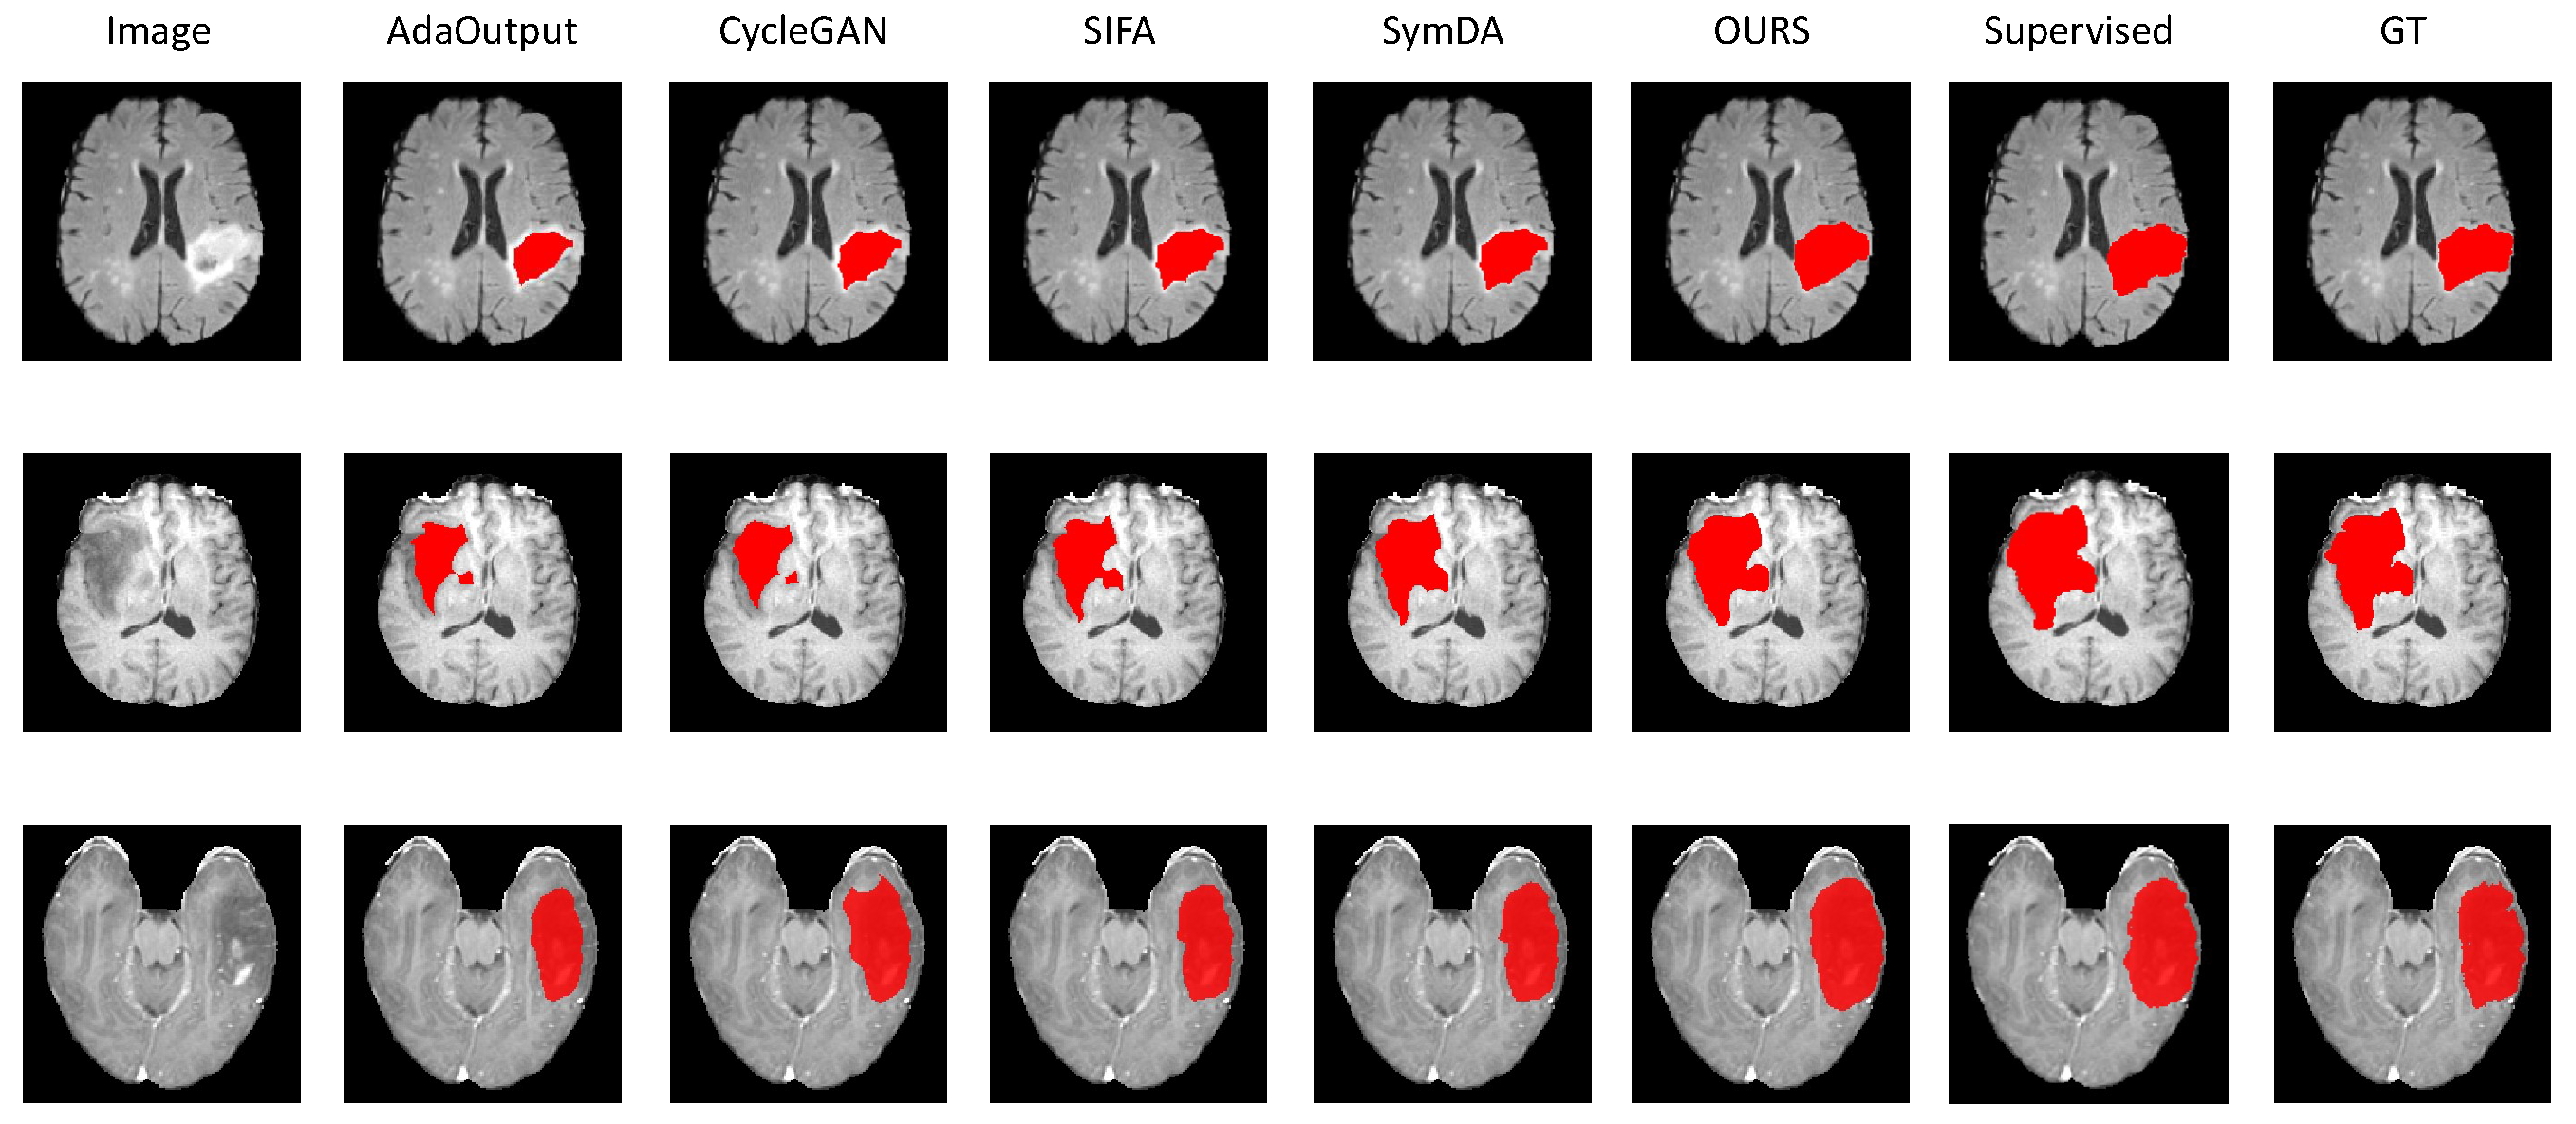

4.2.2. Results on Brain-Tumor Segmentation